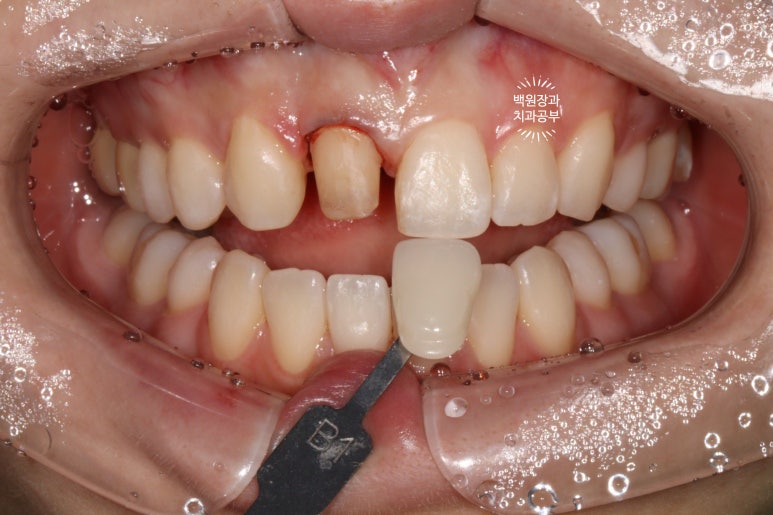

전반적으로 A2.5~A3 shade를 갖던 치아들이, 2시간 정도 전문가 치아미백을 받고 나서

B1보다도 더 밝아졌답니다.

전반적으로 색조가 whitish하게 개선되었네요!

B1임을 측정해서 임시치아를 제작해 붙인채로 약 1달 정도 기다리면 좋습니다!